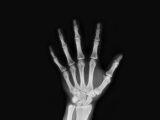

A fim de tratar eficazmente esses problemas médicos, exames preventivos, como a angiotomografia, talvez precisem ser feitos. Esta é uma varredura que produz imagens detalhadas das principais artérias e vasos sanguíneos do corpo.

O objetivo da angiografia por TC é verificar vários tipos de irregularidades, como coágulos sanguíneos, aneurismas e artérias entupidas.

Todas estas coisas têm um efeito direto nas artérias e vasos sanguíneos do corpo, e assim, se um paciente apresentar certos sintomas, uma angiografia por TC será feita para determinar a causa direta dentro do sistema circulatório.